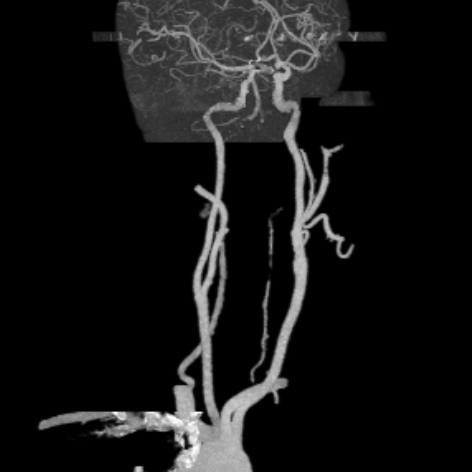

相逢就是缘,有求必全力以赴。立即进行全面评估,CTA和MRI发现颅内多发脑梗塞,脑干为重,双侧椎动脉颅内段基本看不到了,而进一步的DSA造影更为糟糕,左侧椎动脉的颅内颅外段直接全程完全闭塞,右侧颅外剩下一个小尾巴在血液中摇摇欲坠……,诺大的后循环仅仅靠纤细的后交通动脉从前循环借点血液过来,勉强续命,仅仅靠这点前循环的救急,可谓“杯水车薪”,不是“长久之计”,于是决定开通右侧闭塞的椎动脉(颅内+颅外,主要集中在V3+V4段)。

开通这么长节段的夹层所致的椎动脉,说说可以,做起来绝非易事,特别是颅内段,一旦跑到血管外出血,接近脑干,后果严重,谨慎开通的过程还算顺利,微导管带过就是磕磕绊绊不顺利,好吧,小球囊从上到下扩下来,不通,更换稍大球囊扩下来,还是不通,这夹层和狭窄不一样啊,支架导管带过仍然磕磕绊绊,不顺畅,铺开第一个支架,直接来了末端打开不良……,这么长的闭塞段,那得需要多少支架啊?万一放完了,钱花了,不通咋办?

微导管继续超过去,轻轻造影,开通的路径隐约返流闪现,立即改变策略,逆向铺路,开通成功。

术后查房,患者头晕消失,双侧听力基本恢复,整个手术时间历时7个小时,过程是艰难的,结果是欣慰的~~~